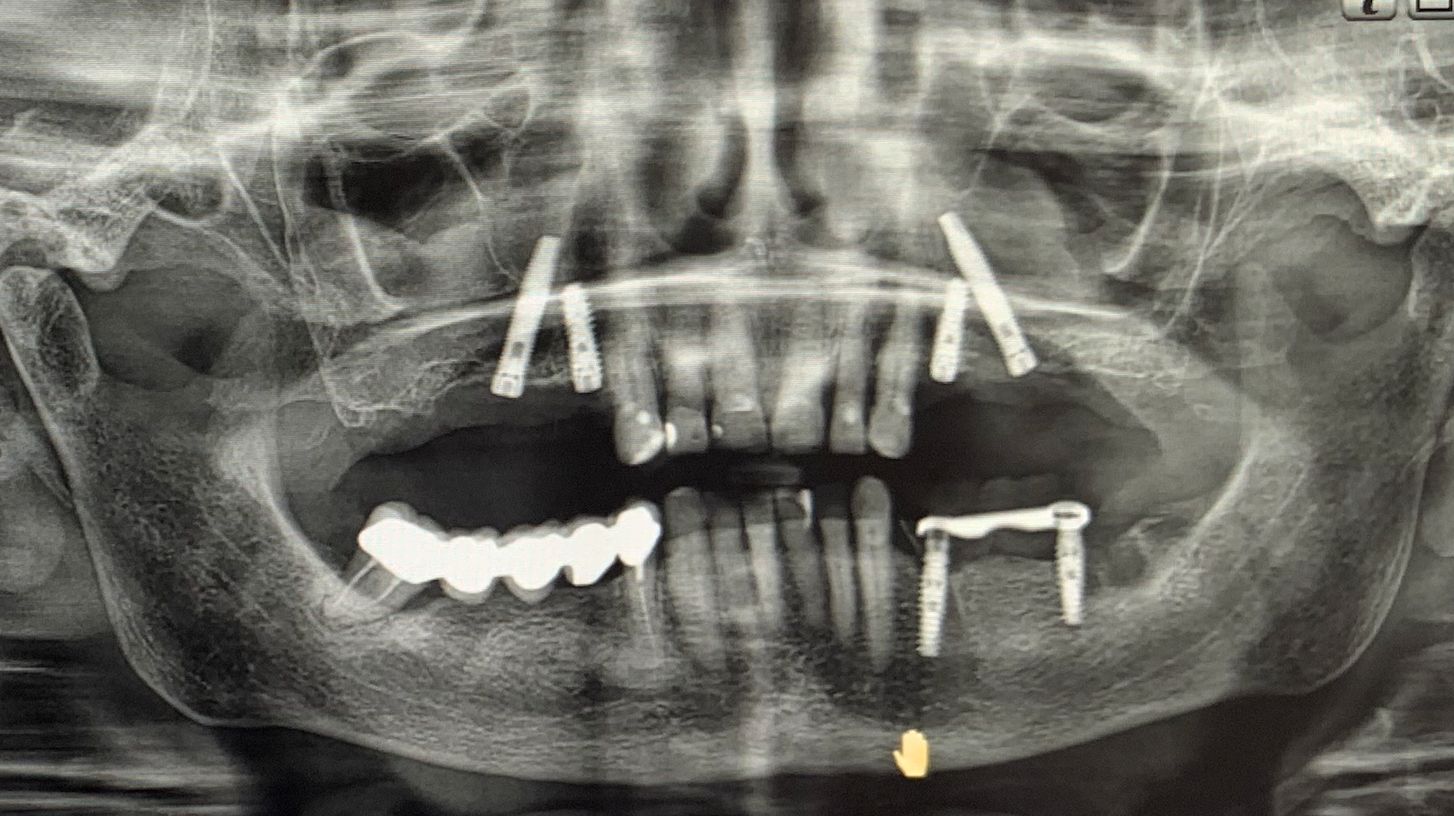

Nei settori posteriori, caratterizzati da significativa atrofia ossea e da pneumatizzazione del seno mascellare, è stato adottato un approccio transinusale. È stata pertanto realizzata una finestra laterale per consentire il sollevamento della membrana di Schneider (Fig. 3), procedura eseguita con particolare attenzione per preservarne l’integrità. Successivamente i siti implantari sono stati preparati con una traiettoria inclinata che attraversa la cavità sinusale, permettendo l'ancoraggio nell'osso basale anteriore. Sono stati quindi inseriti due impianti BT-Rhyno (Fig. 4), progettati specificatamente per l'inserimento transinusale e in grado di garantire adeguata stabilità anche in presenza di ridotto spessore osseo crestale.

Fig. 3 - Membrana di Schneider

Fig. 4 - Impianti BT-Rhyno